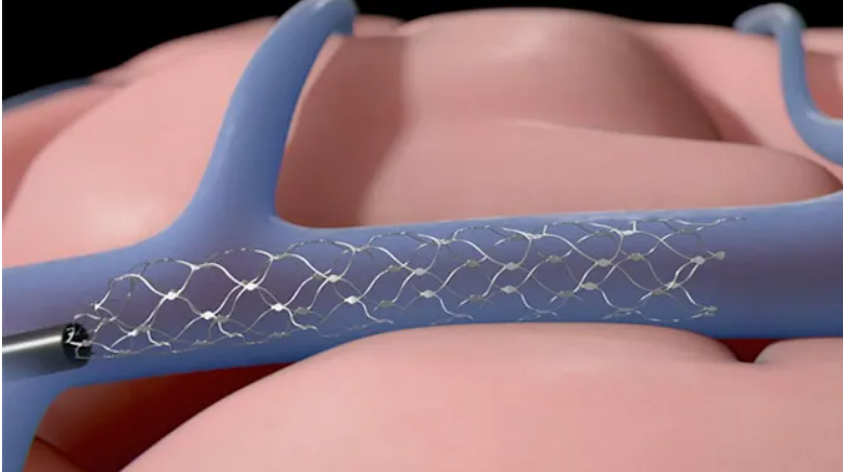

ALS,也被称为Lou Gehrig 's disease,已经导致62岁的奥基夫失去很多运动功能,并使他无法工作。2020年4月,他接受了Stentrode BCI,这是一种通过颈静脉植入大脑的小型支架安装电极阵列。

62 岁的 O'Keefe 因患有ALS,失去很多运动功能,无法工作。2020 年 4 月,他接受了 Stentrode BCI,这是一种通过颈静脉植入大脑的小型支架式电极阵列。

7月份,美国食品和药物管理局批准了一家制造植入式脑机接口(brain-computer interface,BCI)的公司对人类患者进行临床试验。Synchron计划今年晚些时候在纽约Mount Sinai医院对其支架植入物进行早期可行性研究,共有六名受试者。该公司表示,将评估该设备“对严重瘫痪患者的安全性和有效性”。